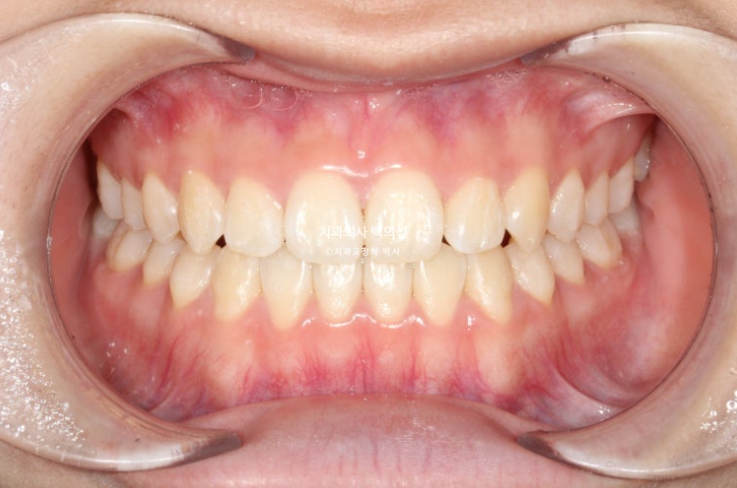

25.04

중심선은 정확하게 맞으며 앞니 교합은 좋습니다.

추가장치를 끼는 동안은 3급 고무줄을 내내 걸면서 앞니 교합 안정을 도모했습니다.